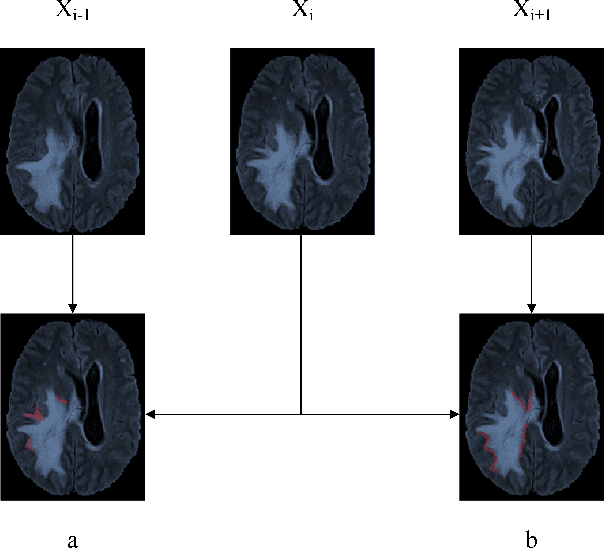

Abstract:Automatic image segmentation technology is critical to the visual analysis. The autoencoder architecture has satisfying performance in various image segmentation tasks. However, autoencoders based on convolutional neural networks (CNN) seem to encounter a bottleneck in improving the accuracy of semantic segmentation. Increasing the inter-class distance between foreground and background is an inherent characteristic of the segmentation network. However, segmentation networks pay too much attention to the main visual difference between foreground and background, and ignores the detailed edge information, which leads to a reduction in the accuracy of edge segmentation. In this paper, we propose a light-weight end-to-end segmentation framework based on multi-task learning, termed Edge Attention autoencoder Network (EAA-Net), to improve edge segmentation ability. Our approach not only utilizes the segmentation network to obtain inter-class features, but also applies the reconstruction network to extract intra-class features among the foregrounds. We further design a intra-class and inter-class features fusion module -- I2 fusion module. The I2 fusion module is used to merge intra-class and inter-class features, and use a soft attention mechanism to remove invalid background information. Experimental results show that our method performs well in medical image segmentation tasks. EAA-Net is easy to implement and has small calculation cost.

Abstract:Automatic segmentation of medical images based on multi-modality is an important topic for disease diagnosis. Although the convolutional neural network (CNN) has been proven to have excellent performance in image segmentation tasks, it is difficult to obtain global information. The lack of global information will seriously affect the accuracy of the segmentation results of the lesion area. In addition, there are visual representation differences between multimodal data of the same patient. These differences will affect the results of the automatic segmentation methods. To solve these problems, we propose a segmentation method suitable for multimodal medical images that can capture global information, named TranSiam. TranSiam is a 2D dual path network that extracts features of different modalities. In each path, we utilize convolution to extract detailed information in low level stage, and design a ICMT block to extract global information in high level stage. ICMT block embeds convolution in the transformer, which can extract global information while retaining spatial and detailed information. Furthermore, we design a novel fusion mechanism based on cross attention and selfattention, called TMM block, which can effectively fuse features between different modalities. On the BraTS 2019 and BraTS 2020 multimodal datasets, we have a significant improvement in accuracy over other popular methods.